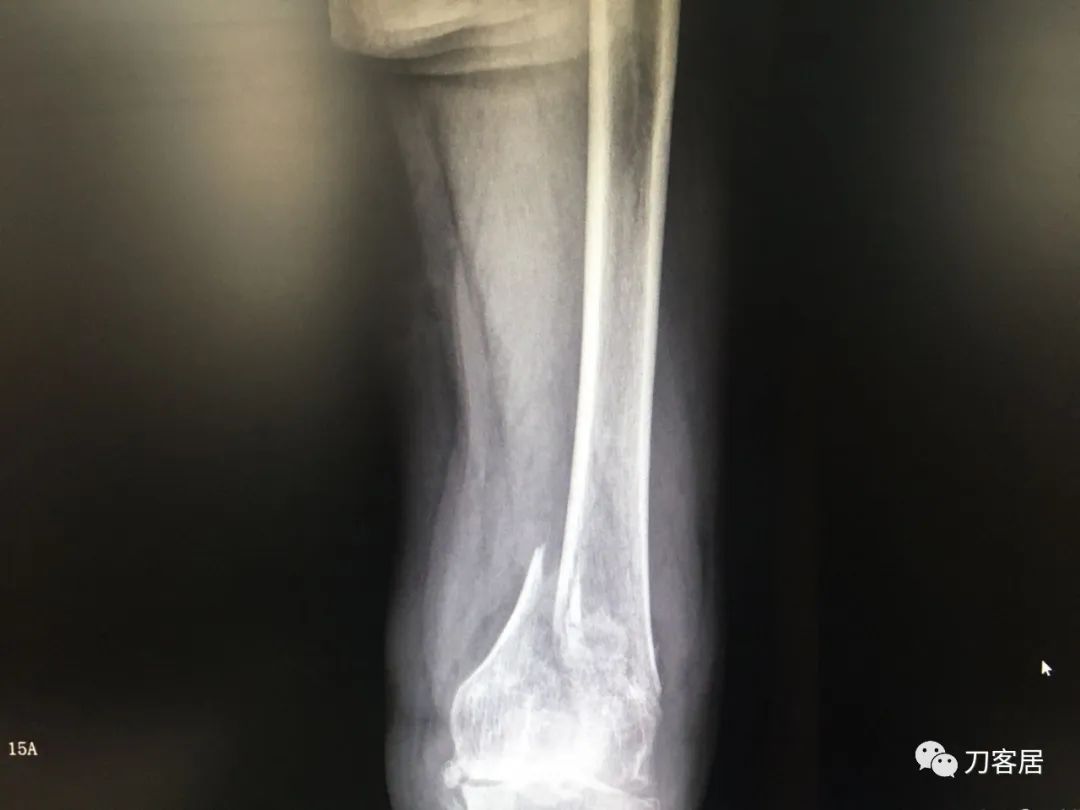

我不是中医黑2: 股骨髁上骨折,中药外敷治疗致股骨髁上陈旧骨折,县级中医医院手术,骨折病例用了骨肿瘤手术关节置换假体。

摘要: 这个病例第一次是摔伤致股骨髁上骨折,不知何种原因患者家属要求保守治疗,外包中药处理后骨折未愈合骨不连,后到一个县级中医院行了关节置换,选择的是肿瘤型假体。

风吹麦浪10:25AM分享个病例,女性,67岁,外院手术后2年,现假体周围骨折。

风吹麦浪10:45AM这个病例第一次是摔伤致股骨髁上骨折,后不知何种原因家属要求保守治疗包中药处理后骨折未愈合骨不连,后到一个县级中医院行了关节置换,选择的是肿瘤型假体。

小土10:48AM患者第一次骨折的片子髌股关节好像不太好

何川11:05AM@长海医院刘忠堂同意,第一张片子显示髁上骨折,当时手术应该恢复最好。但后来拖成陈旧骨折不愈合,这对病人有教育意义。